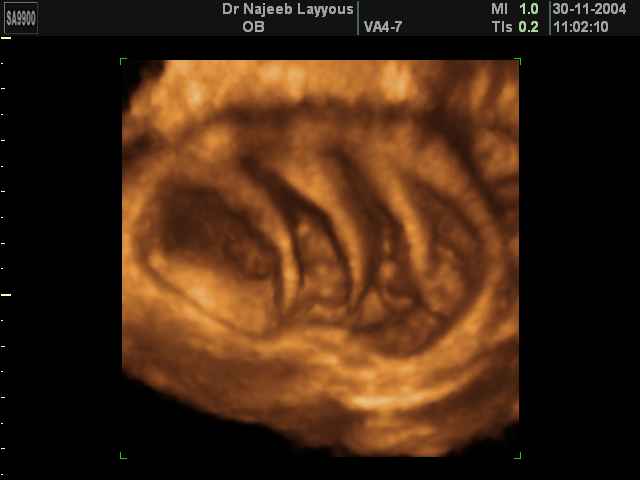

صور لتوائم بجهاز الالتراساوند ثلاثي الأبعاد | الدكتور نجيب ليوس

صور لتوائم بجهاز الموجات فوق صوتية ثلاثي الأبعاد